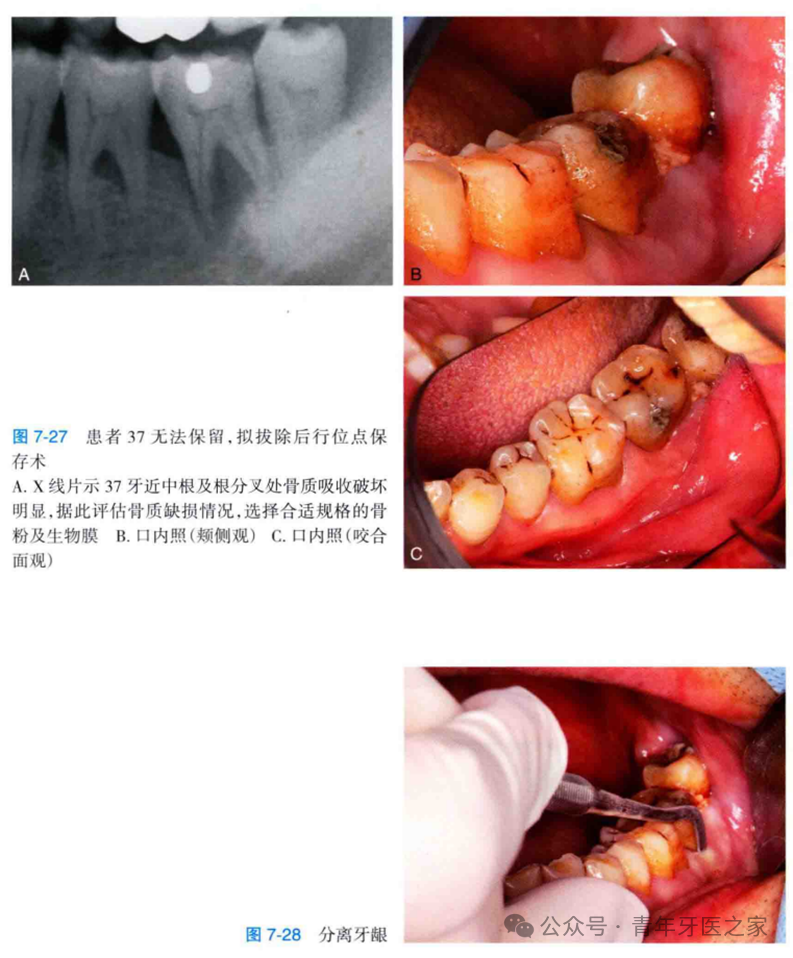

牙外伤及牙源性炎症是引起牙槽骨缺损或缺失最常见的口腔局部因素,如果缺损太多会影响后期的种植及美观。患牙拔除后同期行引导骨组织再生技术,是目前临床上最常见的保持牙槽高度和宽度的方法。

此类患牙由于牙槽骨的缺损拔除并不困难,但为了保证位点保存手术的成功率,拔除患牙后应彻底清理拔牙窝内的异物、炎性肉芽组织及死骨,并用生理盐水冲洗拔牙窝,直至可见拔牙窝骨壁且有新鲜血液从骨壁中渗出。

充填骨粉时,为达到理想的成骨效果,应避免严密填塞,骨粉应与自体血液或血液制品混合后充填,充填量应达到两侧牙槽顶高度。为使成骨在稳定情况下进行,生物膜的屏障作用尤为重要,术中需将屏障膜固定于软组织瓣与牙槽骨骨壁之间,由于翻瓣会加重术区的骨吸收,因此,翻瓣范围应尽可能小,但又能稳定地固定屏障膜。